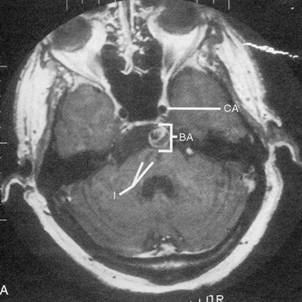

Caso 1 M. A., mulher destra de 74 anos de idade, portadora de fibrilação atrial, caiu abrupta-mente de sua cadeira, ficando impossibilitada de mover seu lado direito. Na emergência onde foi atendida, evidenciou-se uma grande hemiparesia direita associada com hemianopsia ho-mônima direita (amputação de campo visual), impossibilidade de falar e deficiência sensitiva do hemicorpo direito. Os olhos estavam desviados e paralisados conjugadamente para a es-querda. Uma tomografia computadorizada do crânio, realizada 48 horas após o evento, reve-lou uma extensa lesão isquêmica no hemisfério esquerdo, e o exame cardiológico revelou arritmia cardíaca como causa do AVC embólico da paciente. Caso 2 O Sr. A. M., de 44 anos, funcionário de uma fábrica, estava fazendo prateleiras na sua garagem, tarde da noite de um domingo, quando reparou que seu braço e sua perna esquerdos estavam um pouco fracos. Decidiu parar o trabalho, concluindo que estava provavelmente cansado demais e que era hora de ir dormir. Na manhã seguinte, a fraqueza do lado esquerdo estava muito pior. Além disso, a mão direita e a perna esquerda estavam dormentes e formi-gando. Apesar dessas dificuldades, resolveu ir trabalhar naquela manhã, porque não queria perder a festa da aposentadoria de um amigo na hora do almoço. Jurou telefonar para seu mé-dico de família, assim que ele chegasse, para ver se podia consultá-lo ainda naquela tarde. Ao longo de algumas horas, a fraqueza do Sr. A. M. se agravou. Aproximadamente às 10 horas, durante a pausa para o café, ele começou a ter dificuldade para falar. Quando tomou um gole do seu refrigerante, teve dificuldade em engolir e ele começou a tossir. Embaraçado e visi-velmente perturbado, explicou a seus colegas que sua boca “não estava funcionando direito”. Relatou nervosamente a natureza das outras dificuldades que vinha tendo nos últimos dois dias. Comiserado por sua fala visivelmente atrapalhada, um colega se ofereceu para levá-lo ao departamento de emergência do hospital próximo. O Sr. A. M. é um grande fumante (três maços por dia, há 25 anos) e um antigo forte bebedor (duas caixas de cerveja por semana). Relata que não toma mais bebidas alcoólicas, mas continua fumando. O exame físico mostra que o Sr. A. M. pesa 106,5 quilos e tem 1,78 metro de altura. Sua pressão arterial é de 180/110, com freqüência cardíaca em repouso de 93 bpm. O exame físico não apresenta outros achados. O exame neurológico revela que o Sr. A. M. estava alerta, cooperativo, e orientado quanto à pessoa, lugar e tempo. Não foram relatados testes de memória. O exame de nervos cranianos mostrou os seguintes resultados: OLFAÇÃO: não foi testada; VISÃO: campos visuais plenos à confrontação; MOTILIDADE OCULAR: não foi testada; PUPILAS: iguais e reativas ao reflexo direto e consensual à luz. A acomodação não foi testada; TRIGÊMEO: havia sen-sibilidade diminuída à picada do alfinete no lado direito da face. As respostas ao algodão e o reflexo corneano não foram testados; FACIAL: a prega nasolabial direita estava um tanto acha-tada, e a boca caía ligeiramente à direita. A motilidade das sobrancelhas não foi testada; AU-DIÇÃO: o paciente podia ouvir o esfregar dos dedos junto ao pavilhão da orelha. A audição era aparentemente normal nos dois ouvidos; VAGO GLOSSOFARÍNGEO: a voz era normal. O reflexo do vômito e o aspecto dos arcos faríngeos e da úvula não foram testados; ACESSÓRIO: não foi testado; HIPOGLOSSO: a língua desviava para a direita na protrusão. Na avaliação da Postura e Marcha, evidenciou-se que a marcha era ligeiramente atáxica, com base alargada. Incapaz de caminhar atrás de outra pessoa. Conseguia andar nos calcanhares e pontas dos pés, com difi-culdade, e precisava de apoio. A avaliação da motricidade mostrou que a força muscular estava moderadamente fraca (3/5) nas quatro extremidades. Não foram observados movimen-tos anormais. A investigação dos sistemas sensoriais mostrou estar a sensibilidade diminuída à picada de alfinete em todo o lado esquerdo do corpo. A percepção da vibração e da posição das articulações esta intacta bilateralmente. Todos os reflexos de estiramento muscular esta-vam aumentados. O sinal de Babinski estava presente bilateralmente. Havia alguma dismetria nos testes dedo-nariz e calcanhar-joelho, bilateralmente, e disdiadococinesia bilateral. O lado direito estava pior que o esquerdo. A ressonância magnética do crânio (RMC) da cabeça reve-lou que as artérias basilar e vertebral direita eram tortuosas e dilatadas. Foi notado um aneu-risma fusiforme, da porção média à porção superior da artéria basilar, com trombose intralu-minal. Não foi demonstrado sangue extravascular. Evolução: Bem cedo, no outro dia pela manhã, o Sr. A. M. teve vertigem, náusea e vômitos, de instalação súbita. Não podia mais ouvir no ouvido direito. O exame neurológico revelou nistagmo espontâneo do lado esquerdo. No dia seguinte, a audiometria confirmou a perda total da audição à direita. Foi solicitada outra RMC (Figura A). Além das anormalida-des vistas na primeira RMC, a última mostrava duas áreas de sinal diminuído na ponte, ao nível do pedúnculo cerebelar médio. Uma área de sinal diminuído ficava na linha média, a outra estava à direita. Dois dias depois, foi feita uma angiografia cerebral (Figura B). O exame demonstrou alargamento acentuado das artérias basilar e vertebral direita. Também havia evidências de aneurisma fusiforme da artéria basilar com trombose intraluminal. O aneurisma foi considerado inoperável. Foram prescritos ao paciente medicamentos anticoagulantes e terapia ocupacional. Foi aconselhado a deixar de fumar. Ao acompanhamento, dois meses depois da alta (três meses após os sintomas iniciais), o paciente havia melhorado muito. Não fumava mais e havia perdido 15 quilos. Sua pressão arterial era de 130/90 e apresentava 81 bpm cardíacos em repouso. Ainda tinha a perda total da audição no ouvido direito, mas os déficits cerebelares estavam muito melhores. Tinha perda residual moderada da sensibilidade à picada de alfinete do lado esquerdo do corpo. Todos os reflexos de estiramento muscular estavam aumentados, e ele apresentava sinal de Babinski bilateralmente. O diagnóstico defini-tivo foi de aneurisma da artéria basilar e de AVC isquêmico de tronco encefálico.